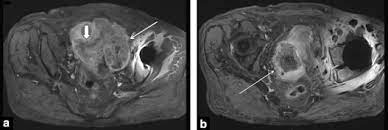

It is the leading cause of gynaecological cancer death in the uk. Ovarian cancer is often difficult to detect in its early stages. The early symptoms are often mild and subtle, and as such, presentation can often be late, with advanced disease. Ovarian cancer has been nicknamed the silent killer because there are said to be few signs and symptoms in the early stages of the disease. Ovarian cancer is a type of cancer that. The optimal abdominal and pelvic ct technique for staging ovarian cancer includes oral contrast media to opacify small bowel and in the absence of contraindications to intravenous contrast media, the use of intravenous contrast media is mandatory. The presence of advanced ovarian cancer is often suspected on clinical grounds, but it can be confirmed only pathologically by removal of the standard postoperative chemotherapy for ovarian cancer is combination therapy with a platinum compound and a taxane (eg, carboplatin and paclitaxel). The female reproductive system contains two ovaries, one on each side of the uterus. Symptoms become more noticeable as the cancer progresses. It is now known, however, that cancers arise from stem cells in tissues, so that failure of differentiation, rather than dedifferentiation of specialized cells, accounts for undifferentiated tumors. Ovarian cancer is a form of cancer that occurs due to abnormal and uncontrolled cell growth in the ovaries. Ovarian cancer is difficult to catch. Any of the tissues of the ovary have the.

If they become infected or inflamed, you have diverticulitis. Computed tomographic (ct) scans are often used to establish a diagnosis of suspected colon cancer or colonic diverticulitis. Do you know what a smear test actually does? Memorial sloan kettering experts discuss ovarian and breast cancer prevention and treatment in women with a brca mutation. When this process begins, there may be no or only vague symptoms. Stage 3 ovarian cancer is in one or both ovaries or fallopian tubes or the lining of the abdominal cavity, which is called the peritoneum. The best course of treatment and the prognosis depend on the stage, type, and grade of the cancer. Ovarian cancer is the medical term for abnormal and uncontrollable cell growth within the ovary that proliferates and spreads to other vital organs. Ovarian cancer is often difficult to detect in its early stages. The female reproductive system contains two ovaries, one on each side of the uterus. Figo ovarian cancer staging effective jan. Find out more about the signs and symptoms of ovarian cancer, stages, and treatment options. Ovarian cancer may be an outcome of numerous environmental, physiological and psychological read this complete plan for diverticulitis diet…